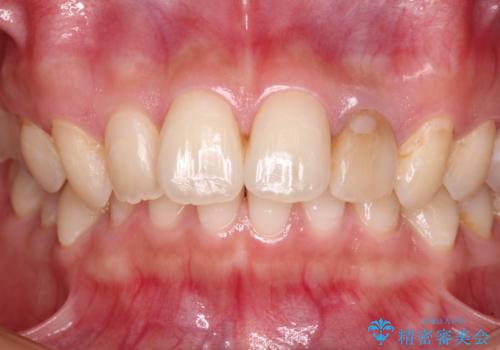

根管治療はやり直さずに、ファイバーポストを使用した土台を植立してオールセラミッククラウンにて補綴することとしました。

神経を取り除いた歯は時間とともに変色してきます。

クリーニングやホワイトニングでは改善できないため、オールセラミッククラウンなどによる補綴治療が必要となります。